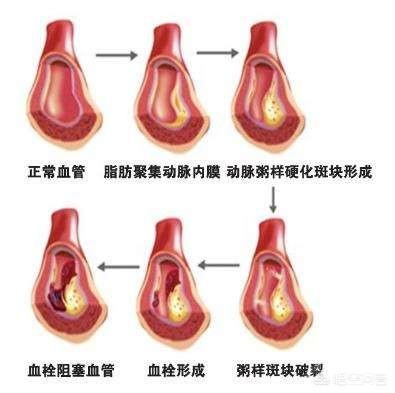

血管狭窄を引き起こし、最も深刻なプラークは、心血管プラーク、または頸動脈プラークであり、これらのプラークの悪化は、心筋虚血、脳虚血につながる;積極的に制御しない場合、あるいはプラークの血栓症の破裂が発生し、心筋梗塞、脳梗塞をもたらす。

高脂血症などの心血管危険因子の影響により、血管の内壁は徐々に傷つき、血液中の余分な脂質は徐々に血管壁の下に沈着し、黄色い粥腫性脂質コアを形成し、最終的には脂質コアに線維性被膜が形成され、これが動脈プラークの形成過程である。 プラークは動脈硬化を引き起こす危険因子であり、安定性や破裂に問題のあるプラークは、反応性血小板血小板の反応性凝集は血栓を形成し、動脈血管を閉塞させ、梗塞性心血管病を引き起こすことさえある。したがって、私たちはプラークの問題に注意を払う必要がありますが、通常、すでに形成されたプラークを元に戻したり除去したりすることは非常に困難であり、私たちがしなければならないことは、合理的な薬物療法と運動によってプラークの形成を予防し、既存のプラークに対して、プラークの安定性を維持するように努め、動脈硬化のプロセスを遅らせ、プラークの破裂がより大きなリスクを引き起こすのを防ぐことです。

プラークは、静脈プラーク、動脈プラークを持って、それは複数の病因因子の役割にある、沈殿物の脂質化のために、単刀直入に言えば、つまり、あなたがより多くのグリース、消化と使用することはできません、血中脂質4と他の多因子の影響下で、内膜に損傷を与え、血管の内層に沈着し、黄色のアテローム性脂質のコアの形成、および最終的に線維性キャップが持続的な炎症にさらされている場合、通常は非常に安定している脂質のコア、上の線維性コアの形成にある攻撃は、飲酒、怒り、夜更かし、少ない水を飲むなど、線維性キャップが破裂し、プラークが流出し、血液中の血小板が結婚フラッシュ、血栓と呼ばれるトラブルメーカーの子供を出産し、この子は、血管をブロックするために悪いことをすることに特化し、トラブルを作るためにさまよう、血管の内腔に血栓が同時に狭くなるだけでなく、破裂、急性心脳血管イベント、脳卒中、心筋梗塞、肺塞栓症、腎不全、静脈瘤などを誘発する。などである。したがって、プラークを除去することは、血管の詰まりを取り除くだけでなく、急性心血管系および脳血管系イベントを予防することにもなり、誰もが関心を寄せている。

動脈プラークは、複数の病因因子の影響下にある動脈内膜の損傷によって引き起こされる一連の炎症反応であり、後に二次的なアテローム性プラークが生成される。プラークの形成は人体にとってより有害であり、同時に血管の内腔を狭くし、破裂して急性心血管系イベントを誘発することもある。したがって、プラークを除去することは血管の詰まりを解消するだけでなく、急性心血管系イベントを予防することにもなり、これはすべての患者の心臓の鼓動である。プラークの治療には、血中脂質、血圧、血糖値などのコントロール、減塩、低コレステロール食、運動量の増加、禁煙、アルコール制限などの悪い生活習慣の改善など、病気の原因から始めるか、上記の治療の上に薬物療法を行うことができます。薬の選択は、アトルバスタチン、レセルプルバスタチンなどのスタチン系薬剤がアテローム性プラークの治療によく使用されます。具体的な治療計画は専門医の指導のもとに立てるべきである。

プラークが発生する過程にはいくつかの段階があり、まず血管の内皮が傷つき、血管内面の保護層が「壊れる」ようになると、血液中の高分子脂肪が低比重リポ蛋白と呼ばれる一種の物質によって血管壁の内膜中膜層に大量に運ばれて蓄積し、血管壁が肥厚し、医療では内膜中膜層が1mm以上になると動脈硬化が起こっていると言われています。内膜中膜層の肥厚が1mmを超えると、局所的に凝集して塊になったような動脈硬化、すなわち初期プラークが生じたといわれる。

初期のプラーク形成は、脂肪の蓄積が一連の炎症反応を引き起こし、実際には、脂肪は常に酸化変性、粥状物質の形成であり、これらの物質は、血管の正常な構造を破壊し、血管の一部となり、この時点で、脂質化された材料は、通常、ソフトスポットと呼ばれる液体の状態にほとんどである。

ソフトスポットの脂質化した物質は、皮膚感染症が膿を出すと線維化し痂皮化するように、時間の経過とともに壊死することがある。また、カルシウムが沈着すると石灰化が起こり、プラークが硬くなり、血管収縮機能がより低下する。このようなプラークはハードスポットと呼ばれる。